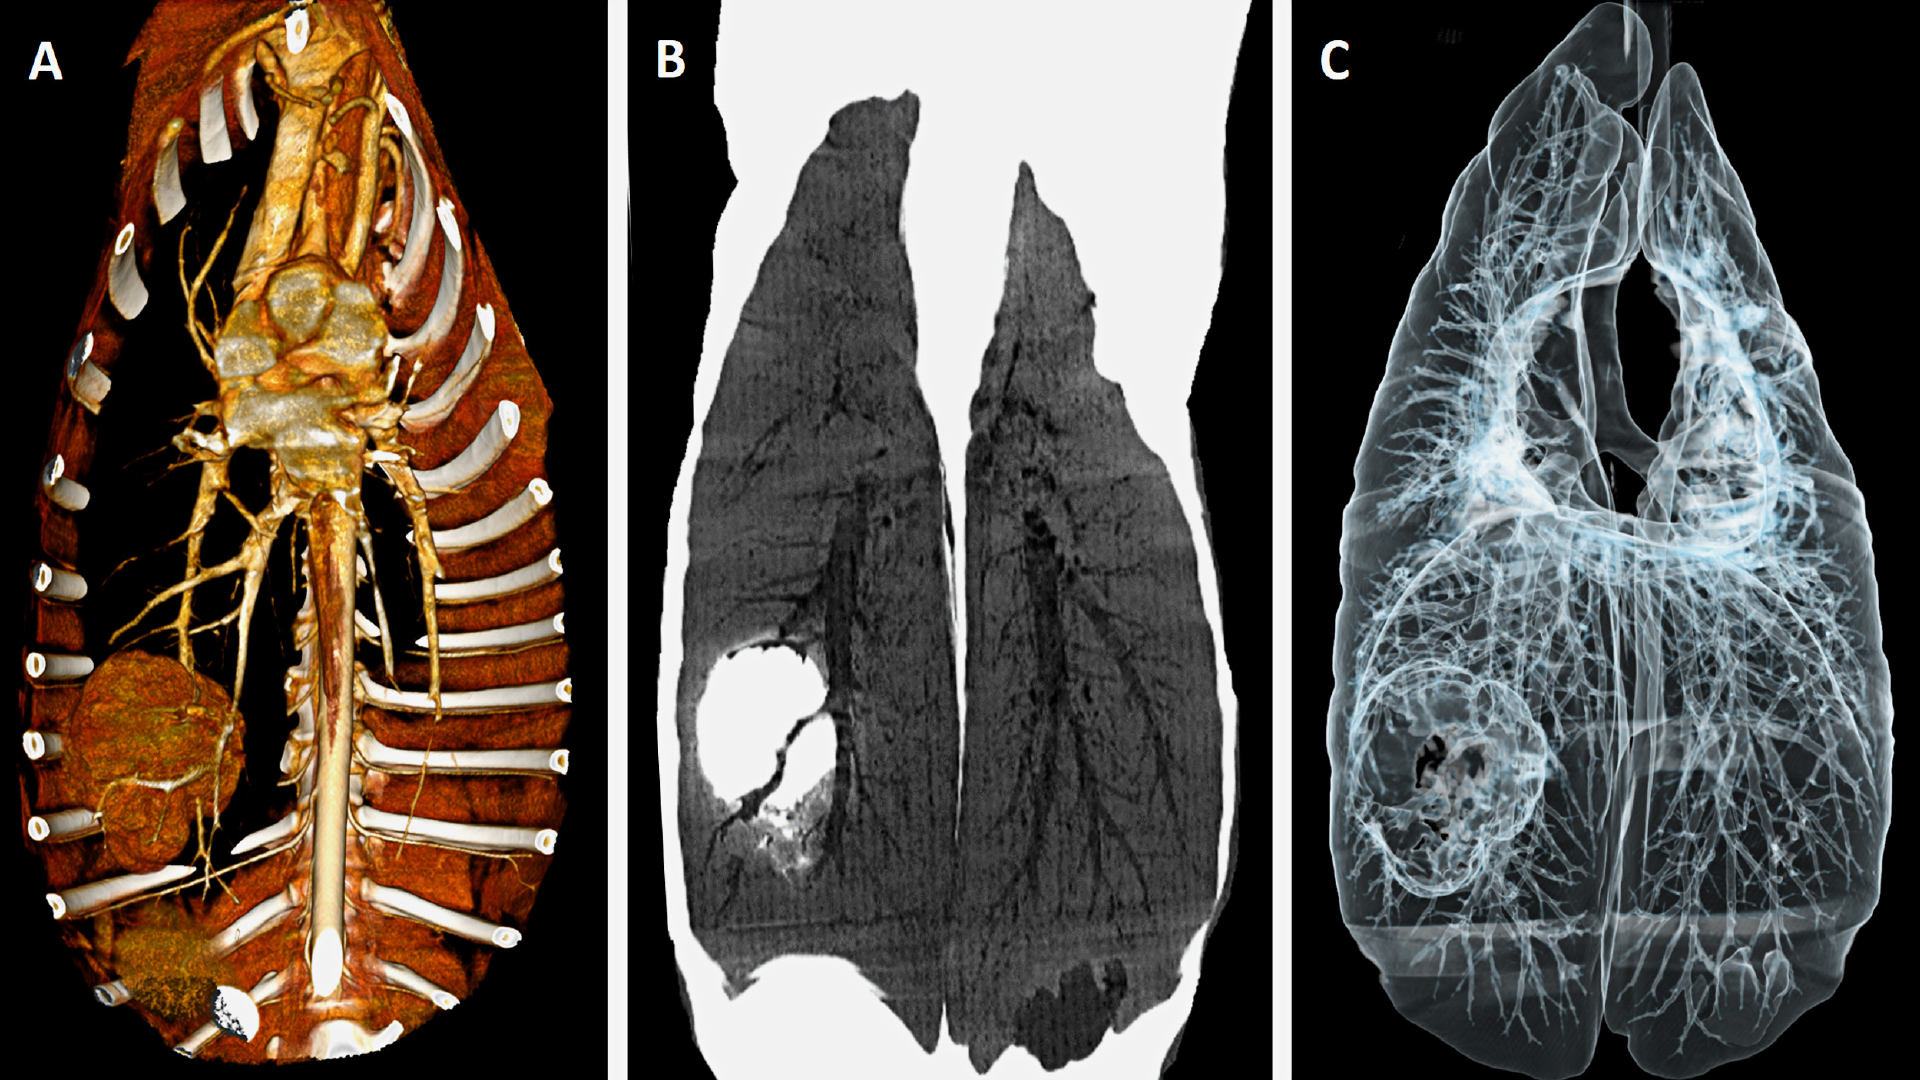

Röntgenuntersuchung vs. Computertomographie

Im Vergleich zur Röntgenuntersuchung ist die CT für die Diagnostik von Lungenläsionen besser geeignet. So konnte in Studien gezeigt werden, dass die CT bei „quantitativem“ Nachweis von Lungenveränderungen sensitiver ist und auch bei der „qualitativen“ Einordnung von Läsionen – der Darstellung morphologischer Merkmale – der Röntgendiagnostik überlegen ist (Nemanic et al., 2006, Alexander et al., 2012, Armbrust et al., 2012). Im Wesentlichen liegt das daran, dass mit modernen Tomographen Schnittbilder mit einer hohen örtlichen Auflösung – im Bereich von ein bis zwei Millimetern – erzeugt werden können. Die in transversaler Ebene erzeugten Bilddatensätze können in der Folge in anderen Schnittebenen neu angeordnet werden (multiplanare Reformation) sowie mithilfe von Nachverarbeitungsalgorithmen anderweitig dargestellt (Erzeugung von 3D-Datensätzen) und analysiert werden (spezifische Darstellungen der gemessenen Schwächungsprofile, Abb. 1).